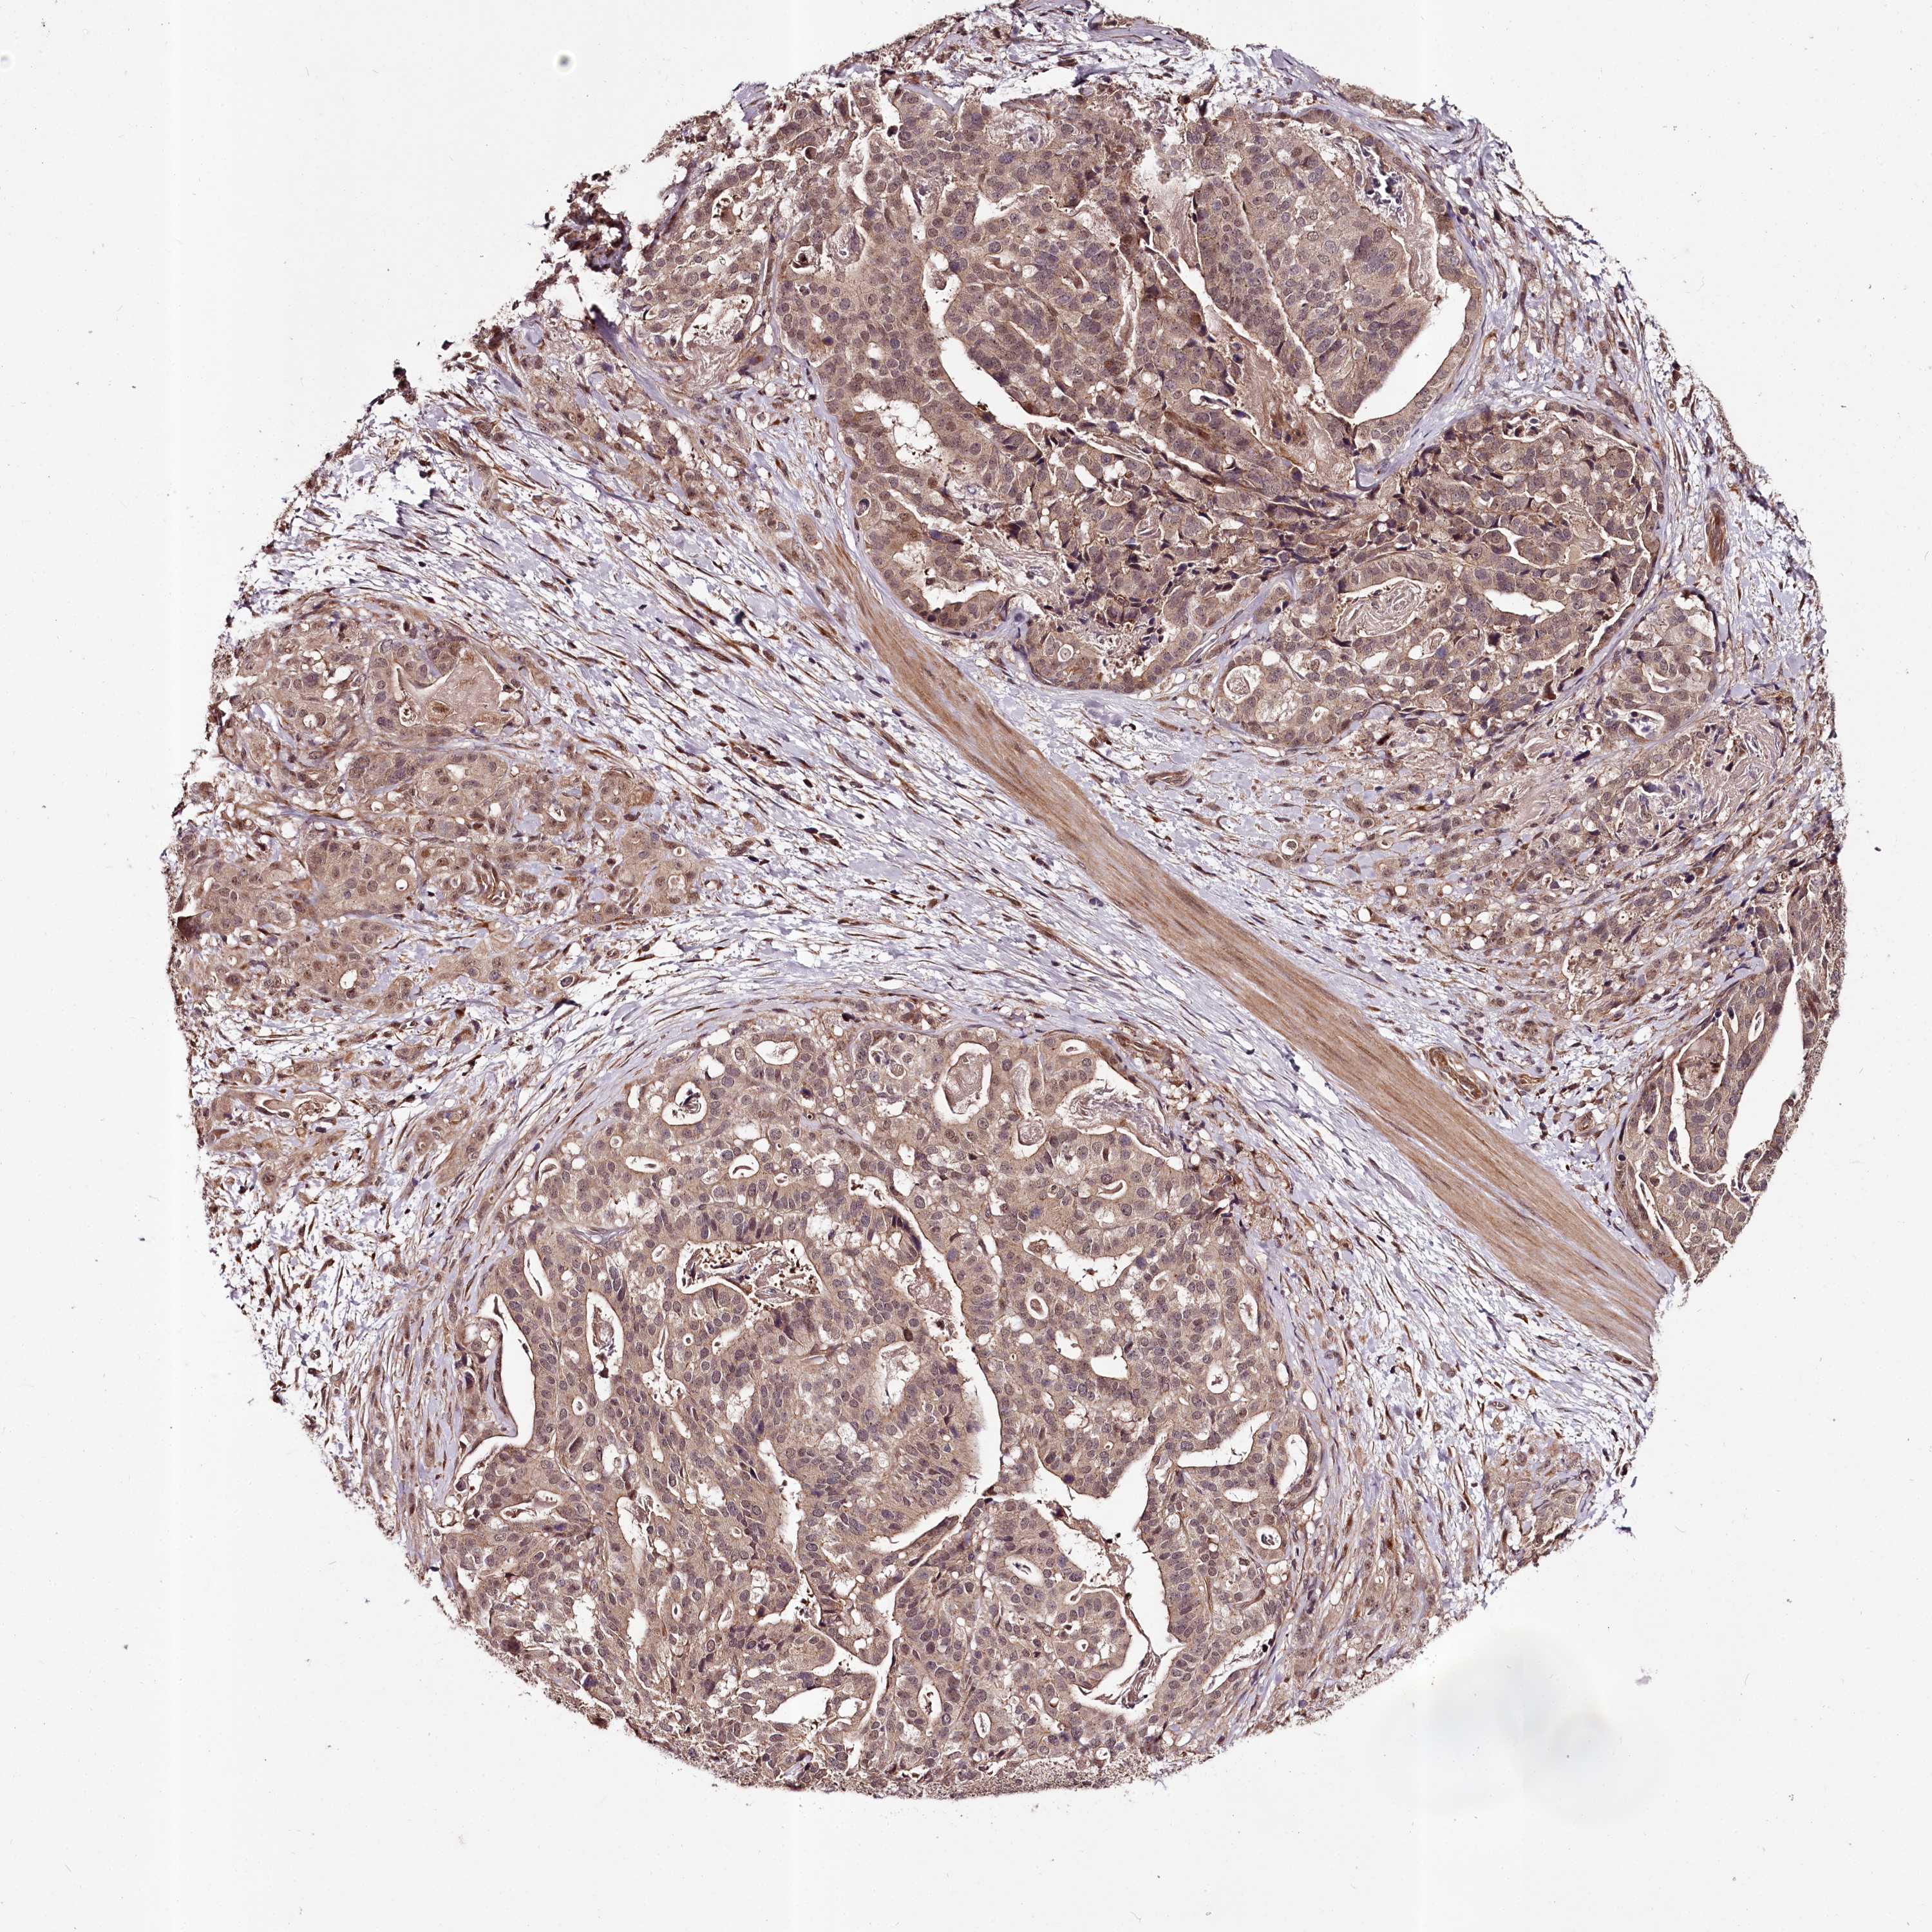

STOMACH CANCER - Protein expressioni

A mouse-over function shows sample information and annotation data. Click on an image to view it in a full screen mode. Samples can be filtered based on level of antibody staining by selecting one or several of the following categories: high, medium, low and not detected. The assay and annotation is described here.

Note that samples used for immunohistochemistry by the Human Protein Atlas do not correspond to samples in the TCGA dataset.

Antibody stainingi

Antibody staining in the annotated cell types in the current human tissue is reported as not detected, low, medium, or high, based on conventional immunohistochemistry profiling in selected tissues. This score is based on the combination of the staining intensity and fraction of stained cells.

Each image is clickable and will lead to virtual microscopy that enables deeper exploration of all samples and also displays staining intensity scores, fraction scores and subcellular localization as well as patient and tissue information for each sample.

Antibody HPA037717

Staining

High

Medium

Low

Not detected

Intensity

Strong

Moderate

Weak

Negative

Quantity

>75%

75%-25%

<25%

None

Location

Nuclear

Cytoplasmic/membranous

Cytoplasmic/membranous,nuclear

Adenocarcinoma, NOS

Adenocarcinoma, High grade